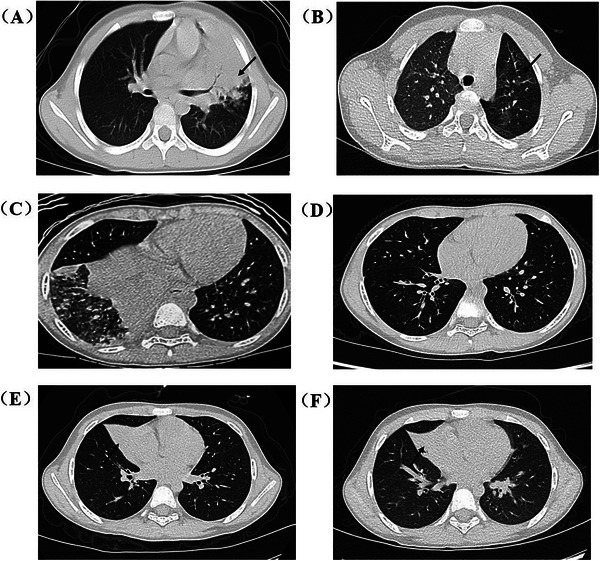

Methods: This randomized, parallel-controlled, multicenter clinical trial was conducted in mainland China and enrolled pediatric patients hospitalized with severe MPP. A total of 424 enrolled patients were randomized (allocation ratio of 1:1) to azithromycin combined with either a low-dose [2 mg/(kg·d)] or a high-dose [10 mg/(kg·d)] methylprednisolone treatment for 3 d followed by tapering over 12 d. The primary outcome was the incidence of composite adverse outcomes, including atelectasis, bronchiectasis, or bronchiolitis obliterans 6 months after treatment.

Results: A total of 118 (27.8%) developed adverse pulmonary lesions at 6 months after treatment; 66 of 211 (31.3%) in the high-dose methylprednisolone group and 52 of 213 (24.4%) in the low-dose group, respectively. The risk ratio of long-term pulmonary lesions in a high-dose group to those in a low-dose group was 1.28 (95% confidence interval [95% CI]: 0.94-1.75). In addition, the risk of hypertension in the high-dose group (8.1%, 17 of 211) was higher than that in the low-dose group (1.4%, three of 213), with a risk ratio of 5.72 (95% CI: 1.70-19.23).

Interpretation: Azithromycin combined with low-dose methylprednisolone demonstrates non-inferior efficacy in reducing pulmonary lesions at 6-month follow-up compared to combined with high-dose methylprednisolone while exhibiting a more favorable safety profile.